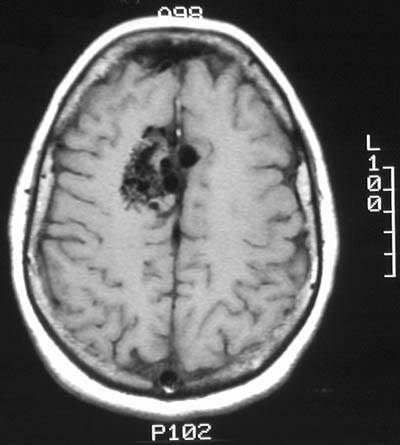

There is a vascular malformation in the right medial frontal lobe, as seen above in sagittal view with T1 weighted MRI scan. The lesion is seen below in axial view with T1 and T2 weighted MRI scans. Note the large, irregular vascular channels.